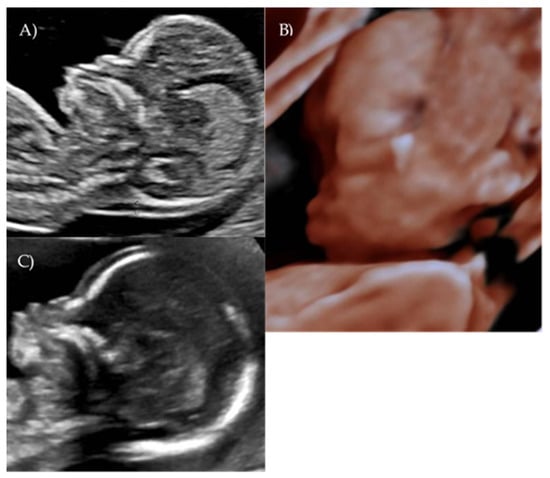

Her first-trimester combined screening for aneuploidies was low risk for trisomy 21, 18, and 13, and preterm preeclampsia. The nuchal translucency was within normal ranges (Figure 1A).

A detailed ultrasound scan was performed at 21 weeks and 1 day of gestation at our fetal medicine unit. Nasofrontal angle, nasal bone, and maxillary width were measured and compared to published references to unaffected fetuses at similar gestational ages [12,13]. Facial dysmorphism was further investigated by 3D scan (Figure 1B) through multiplanar mode and surface rendering, which allowed a more realistic representation of the fetal face, thus allowing characterization of the defect.

A flattened fetal facial profile with a nasal-frontal angle of 152.18° (cut-off: <143°, [14]), consistent with Binder-type maxillonasal dysplasia, was confirmed. To identify any other structural abnormalities, detailed examinations of the fetal anatomy and a fetal echocardiogram were conducted. No additional structural anomalies were identified (Figure 1C).

Figure 1. Case 1. (A) First-trimester 2D ultrasound Fetal profile. (B) Flat fetal profile, 21 weeks and 1 day, 3D reconstruction. (C) Nasal-frontal angle: 152.18°.